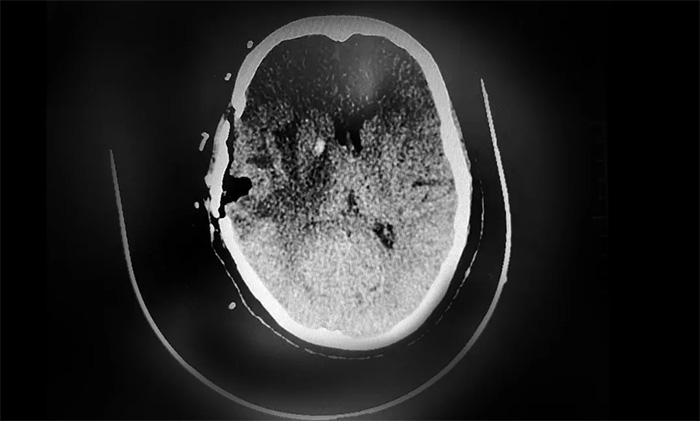

▲ CT复查示,肿瘤已被切除

根据初步病理检测报告,送检的样本为颞叶转移癌,结合病史及免疫组化,符合乳腺癌转移。后续,卢云鹤博士将根据分子病理检测结果,为患者制定实施包括靶向治疗等多学科联合的个体化综合治疗方案,改善患者生存状态,延长生存期。